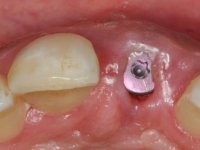

3) Colocação de um implante no espaço criado na zona do 21 associada a uma regeneração óssea guiada da zona,

4) Reabilitar prostodonticamente o implante com um coto de oxido de zirconio e uma coroa de cerâmica vítrea prensada de dissilicato de lítio no sentido de obter o resultado estético pretendido.

Os cotos de óxido de zircónio são dos assuntos mais debatidos em implantologia. A sua resistência à fractura, as conexões externas e internas, a interacção entre o parafuso de retenção e o coto – todos estes assuntos são abordados repetidamente. No entanto, todos parecem concordar que os cotos de óxido de zircónio apresentam resultados altamente previsíveis, especialmente na restauração de dentes anteriores. Outro argumento em favor dos cotos de óxido de zircónio é a alta biocompatibilidade do material.

A comparação entre o óxido de zircónio e o dissilicato de lítio mostra que o último pode sofrer ataque ácido e ser silanizado e assim ser preparado para uma cimentação adesiva. Uma dica: no sentido de criar no coto de óxido de zircónio uma superfície susceptível de ser gravada pelo ácido, a superfície a ser colada pode ser recoberta com uma fina camada de cerâmica de adesão antes de modelar a coroa. Para este propósito, a ceram Zirliner é aplicada primeiro, depois aplica-se uma camada de ceram de dentina profunda na tonalidade desejada. Como resultado, a cor da dentina ilumina a restauração a partir do seu interior e cria a possibilidade de ser aplicado um protocolo de cimentação adesiva.